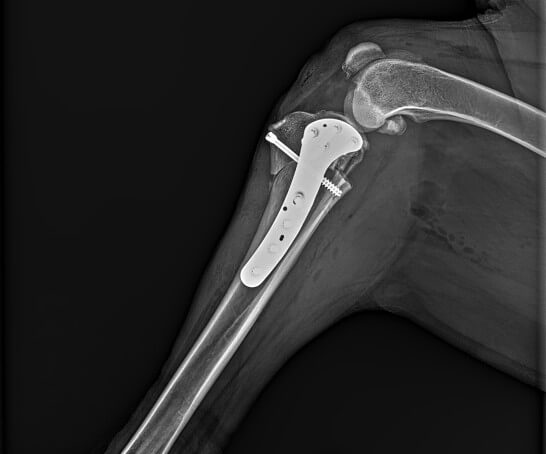

Dr. Gordon Armstrong and Dr. Chad Pilgeram (Pet Orthopedics) provide orthopedic services at our hospital including TTA and MLP surgeries. Client education, pain management, customer satisfaction, and patient outcome have been a huge part of Indian Trail Animal Hospital’s Orthopedic success in and around the greater Spokane area. Dr. Brown, our founding doctor, dedicated a large portion of his veterinary career to orthopedics and post- operative care. We are proud to continue to offer these services in his honor.